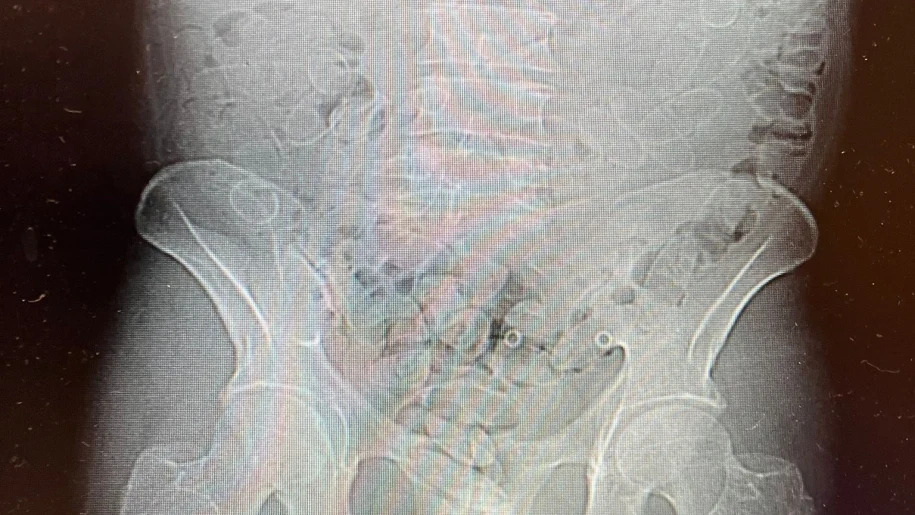

Подальше обстеження за допомогою ультразвуку показало, що затриманий проковтнув ще 88 капсул із наркотиками, намагаючись приховати їх від контролю. Загалом у 89 капсулах містилося близько 800 грамів кокаїну.